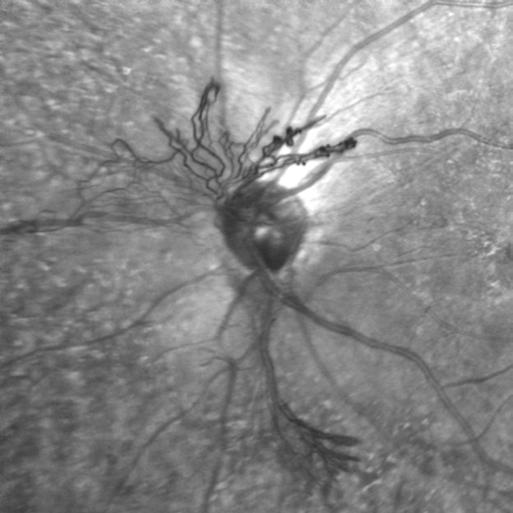

OCT Angiography

NVD

Darrin Landry, CRA, OCT-C, FOPS

Bryson Taylor, Inc.

Saco, Maine